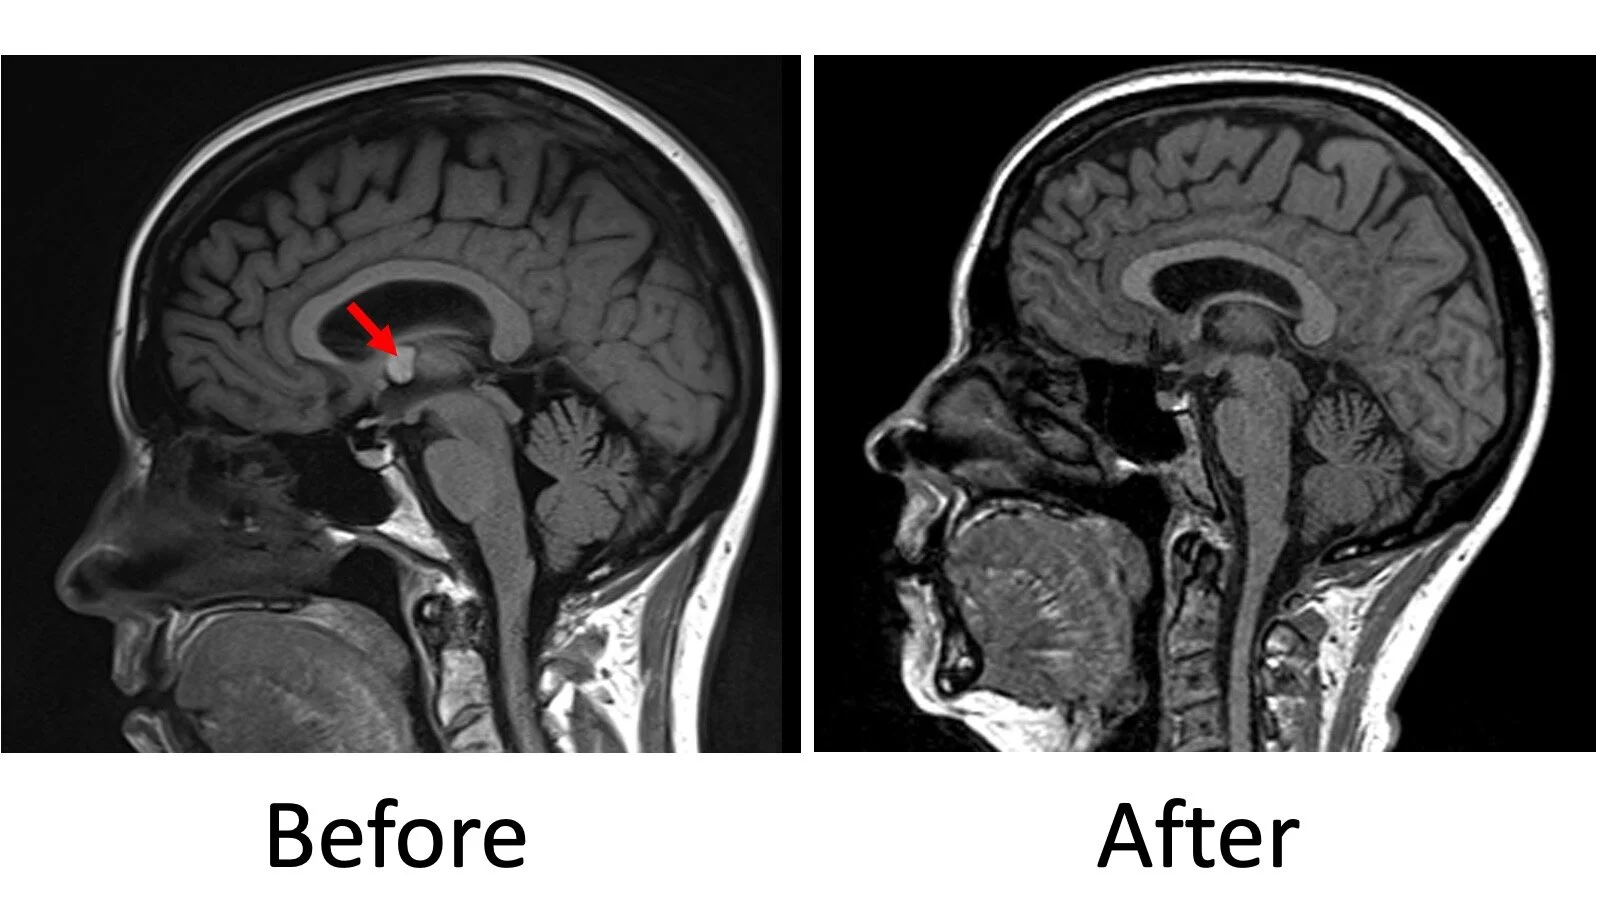

Before and after endoscopic removal of a colloid cyst (red arrow).